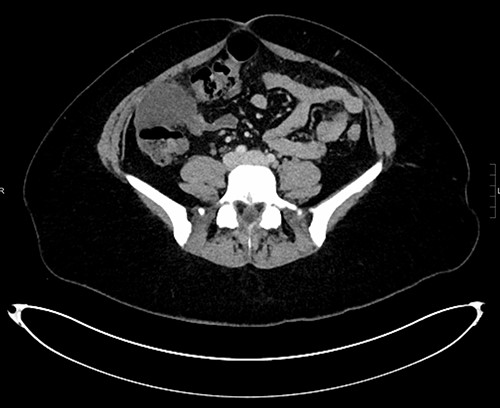

The white cell count was 10.5 × 109/l, C-reactive protein 6.8 mg/l, B-hCG negative, urine culture negative. Ultrasound (US) abdomen did not identify the appendix or the right ovary but noted a 102 × 43 × 52 mm complex multi-locular cyst. Computed tomography (CT) abdomen showed a focal low-density mass with adjacent inflammatory change anterior to the ascending colon measuring 43 × 55 × 54 mm (Figs 1–3). This mass appeared separate to the ovary and the appendix.

Sagittal CT reconstruction highlighting location of mass anterior to ascending colon.